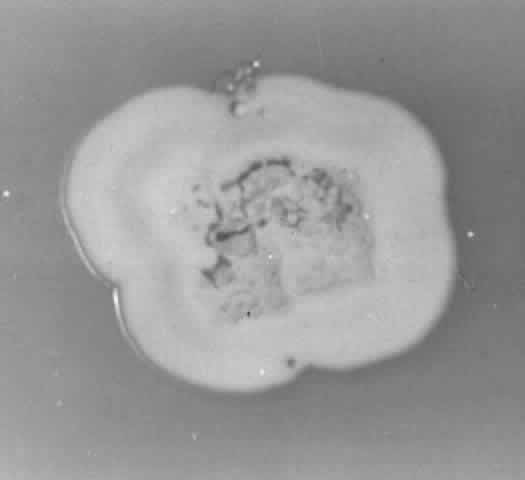

NOCARDIA SPECIES.

Growth occurs on Sabourauddextrose agar without antibiotics, Lowenstein-Jensen medium, and Middlebrook 7H11 agar and matures within 7 to 9 days. Colonies on Sabouraud dextrose agar are white to orange, raised, irregular or smooth (Fig. 9). Microscopically on tap water agar are seen thin, delicate, branching, beaded filaments that fragment into bacillary or coccoid forms (Fig. 10). They are gram positive and may be partially acid fast. There are three major pathogens to humans: N. asteroides, N. brasiliensis, and N. otitidiscaviarum.

Fig. 9. Colony of Nocardia asteroides on Sabouraud dextrose agar.